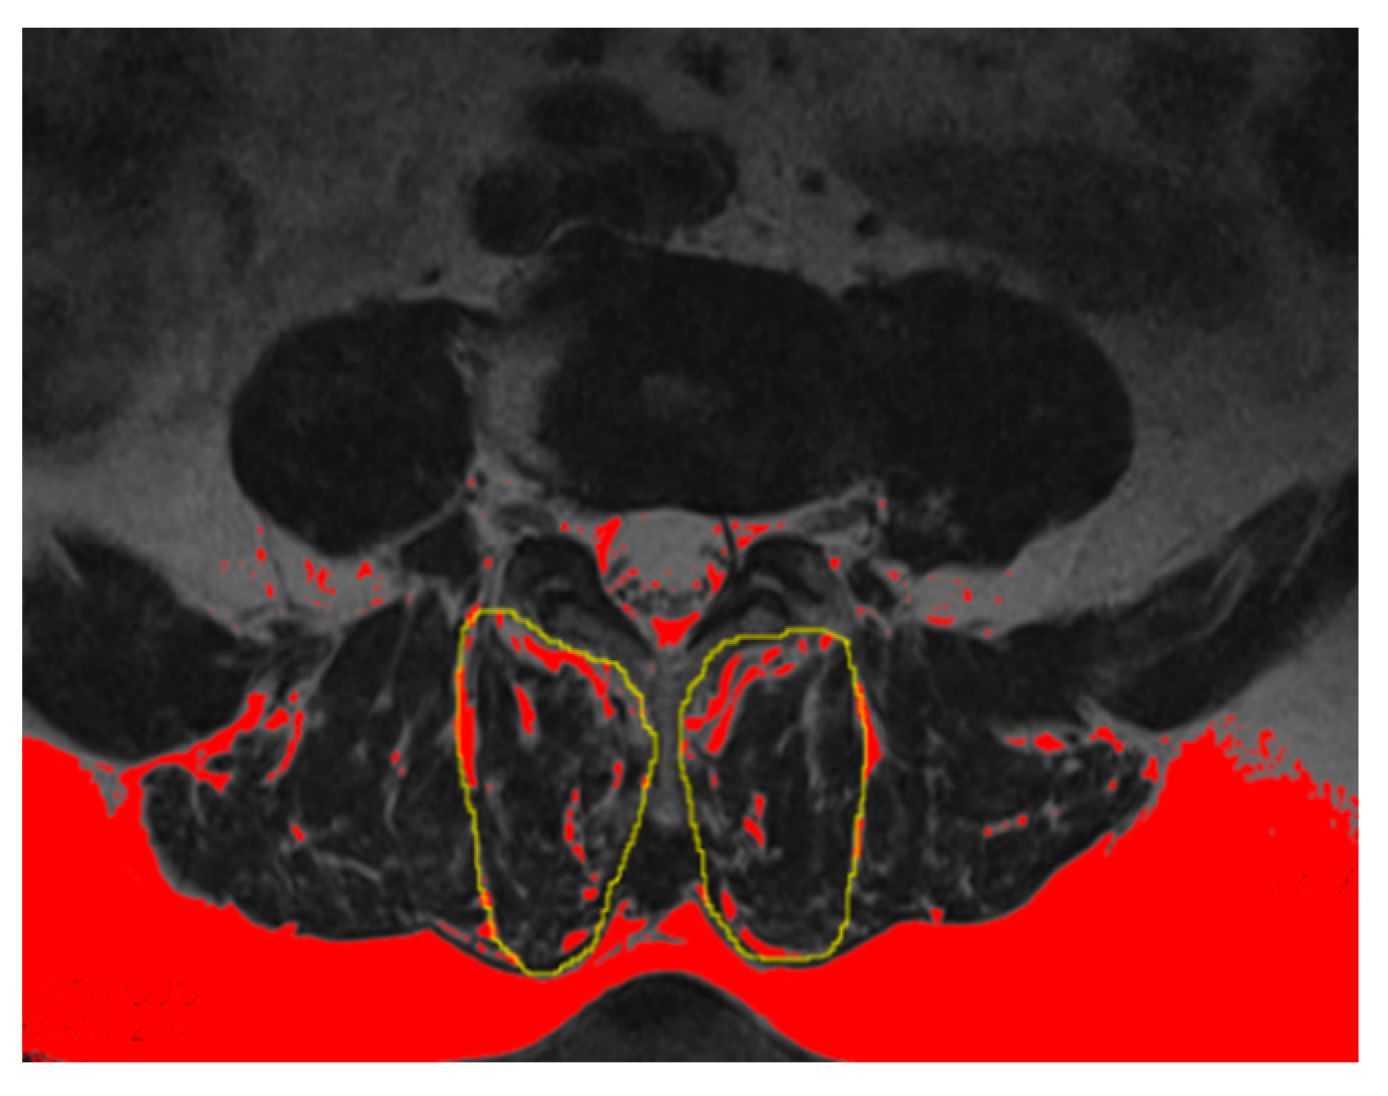

2.4.4. Evaluation of PVM Change

3.2.2. Evaluation of PVM Change

4.6. Correlation between Different Imaging Parameters in the Two Groups